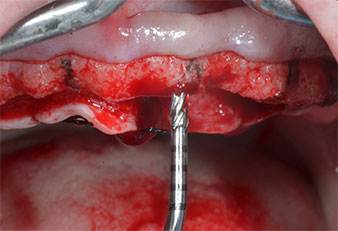

Un insert piézoélectrique diamanté de forme effilée (Piezomed I1) a été utilisé pour marquer les positions implantaires et effectuer la préparation pilote (Fig. 3). On a pris soin de travailler selon un mouvement ascendant et descendant, à puissance réduite, irrigation complète et basse pression (moins de 300g). Ensuite, un insert pilote (Piezomed I2A/I2P) a été utilisé pour l’agrandissement initial de 2mm du diamètre des sites implantaires (Fig. 4), suivi d’un insert de 3mm (Fig. 5).

En cas de densité osseuse élevée, il convient d’utiliser toute la gamme d’inserts, y compris les inserts intermédiaires Piezomed Z25P et Z35P afin d’élargir

les ostéotomies avant l’étape d'agrandissement suivante.

Ces inserts sont également indiqués pour les préparations à proximité de la membrane sinusienne dans le cadre

de procédures d’élévation par voie interne ou lorsque

la hauteur osseuse résiduelle est inférieure à 4mm.

Dans le cas présent, les inserts Z25P et Z35P n’ont pas été utilisés car l’os postérieur était relativement mou

et l’intervention sur celui-ci a été aisée avec le I3A/I3P.